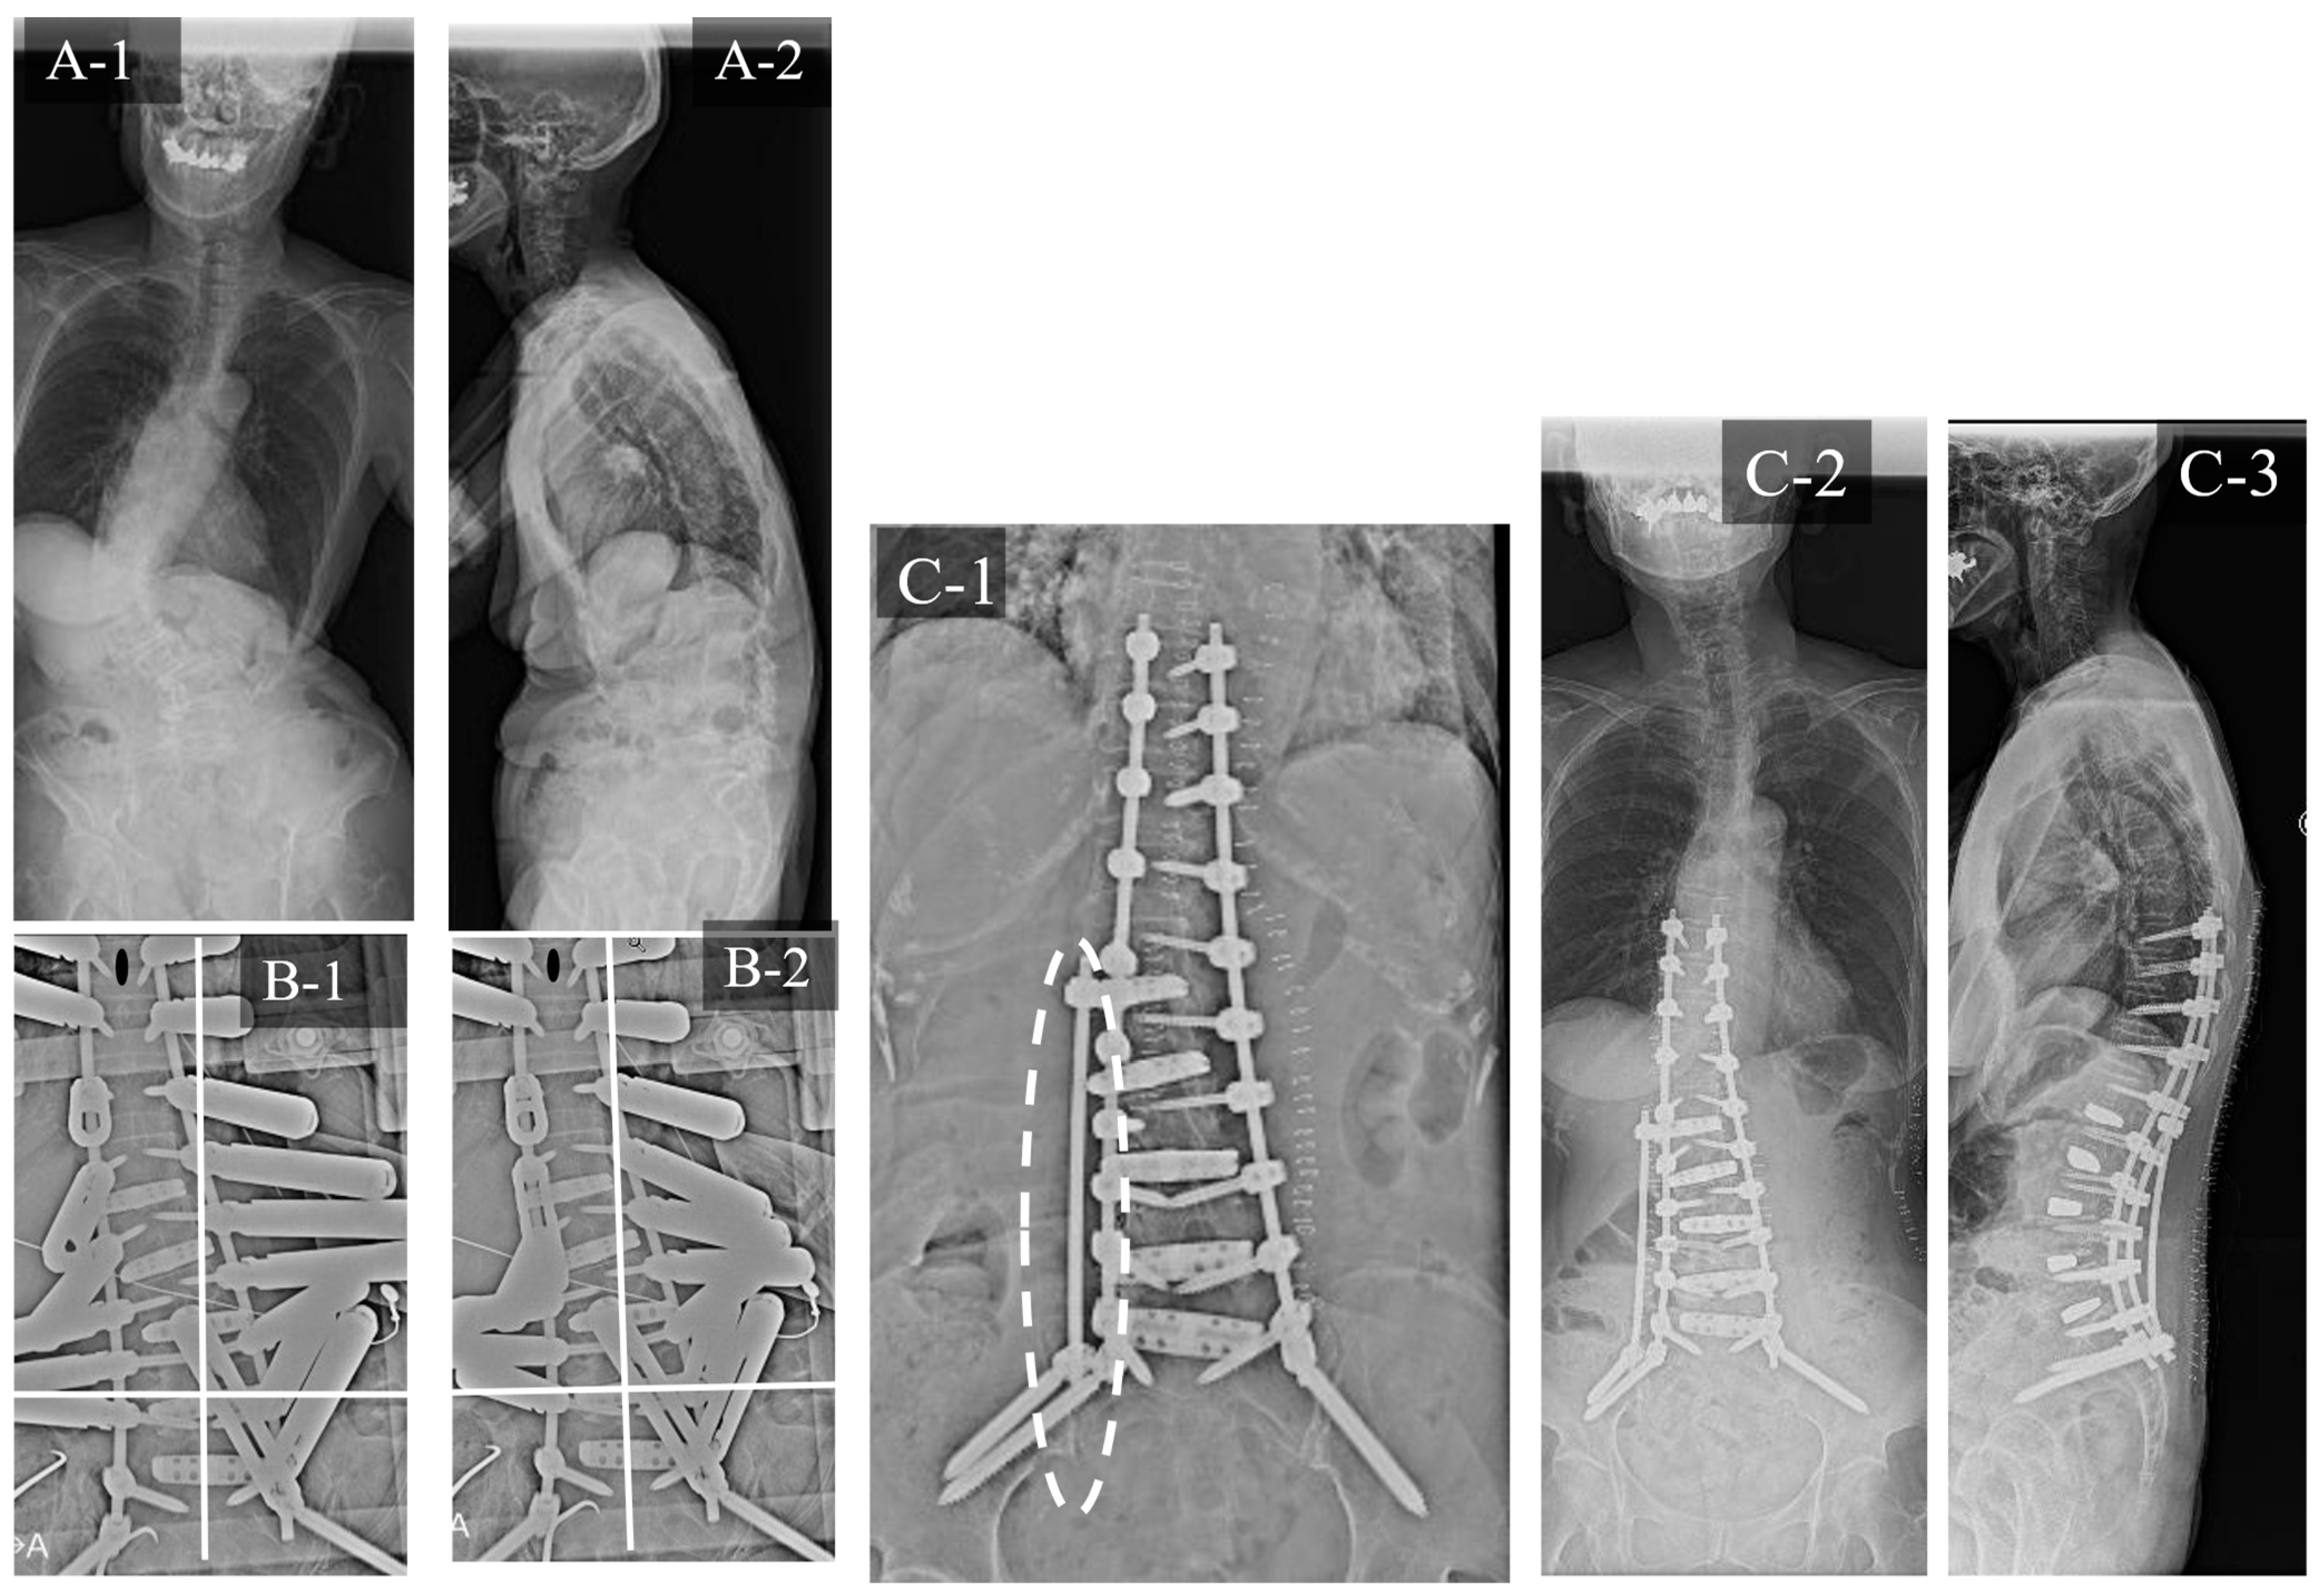

3.1. Case Study 1: RR